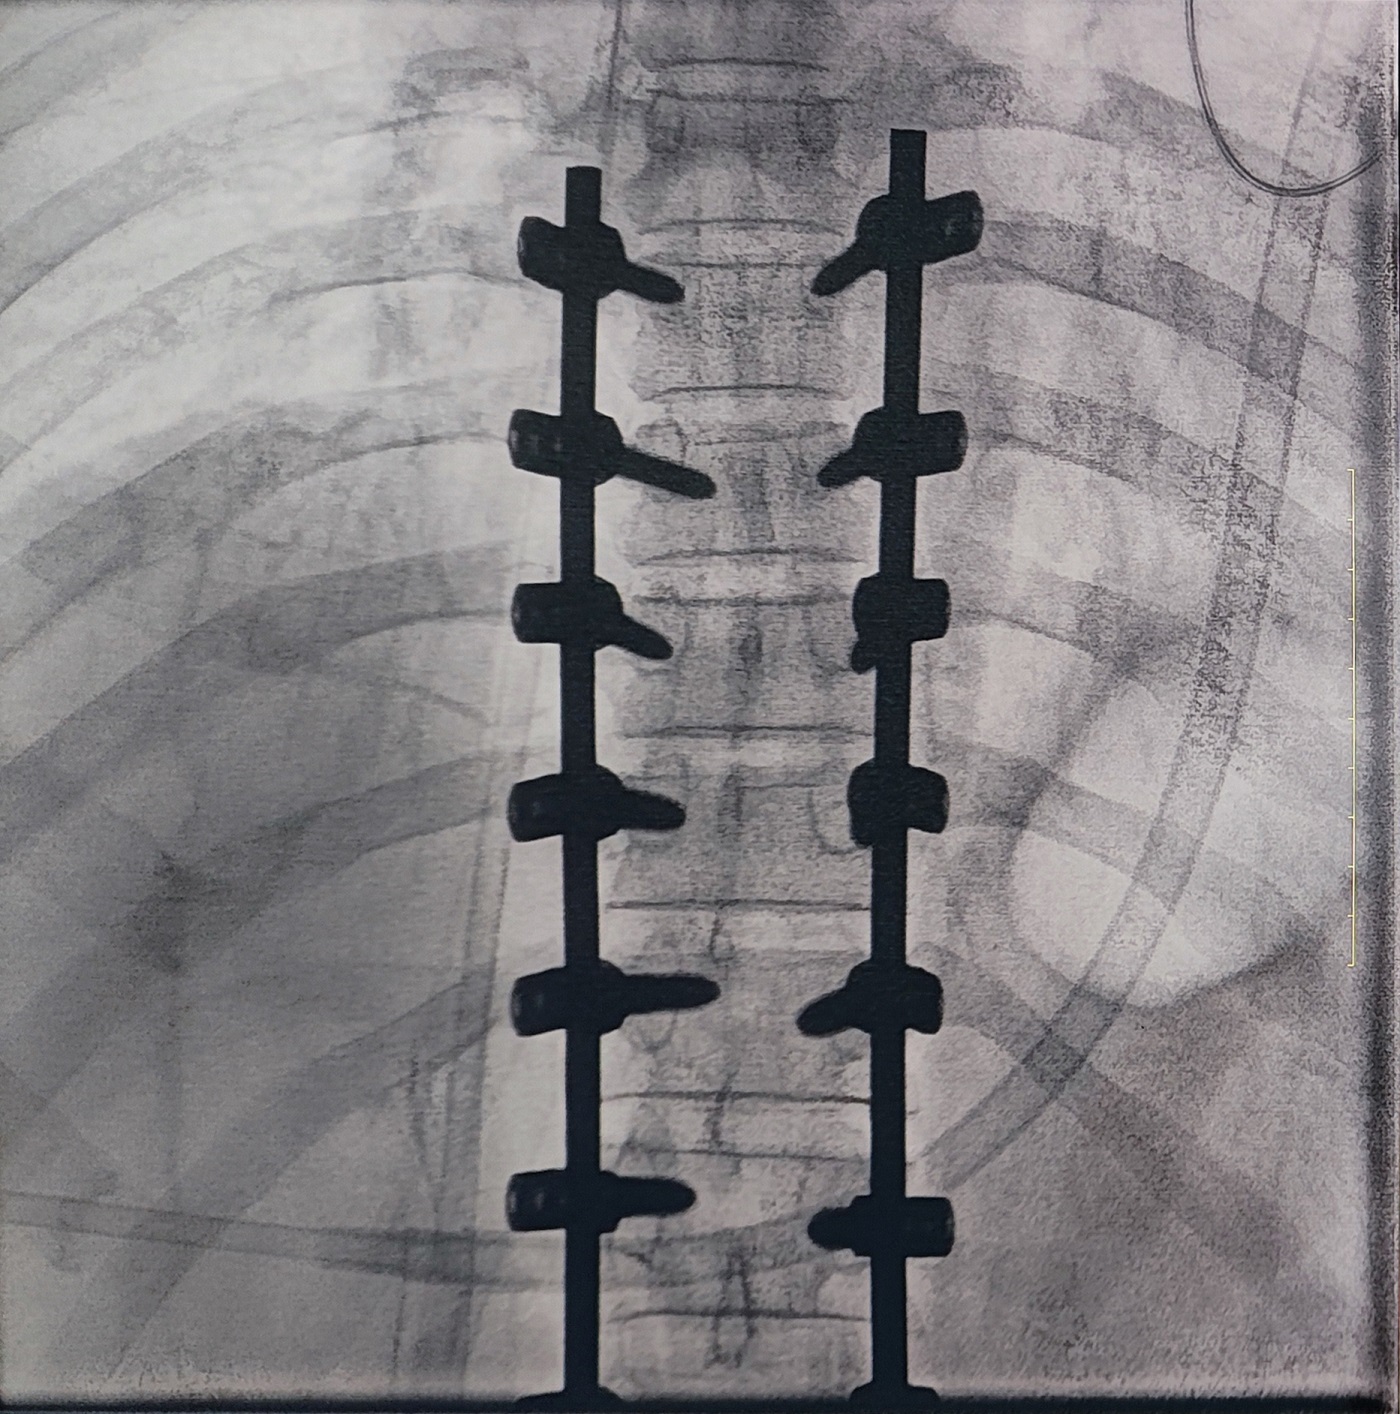

一場脊柱手術(shù)中,醫(yī)生需要拍攝跨越7個節(jié)段的脊柱影像,由于曝光的視野較大,常規(guī)視野的C形臂通常需要拍攝2-3次,普愛醫(yī)療大平板一體式C形臂30CM*30CM的“大視野”,輔助醫(yī)生一次性完成了7個節(jié)段的拍攝。最終,醫(yī)生在高清影像的輔助下完成了14枚螺釘?shù)木珳?zhǔn)定位、置入。

大視野,不僅意味著醫(yī)生可以更快,獲取更全面的影像信息,做出精準(zhǔn)判斷,無需多次拍攝定位,也顯著地降低了患者接受的輻射劑量。